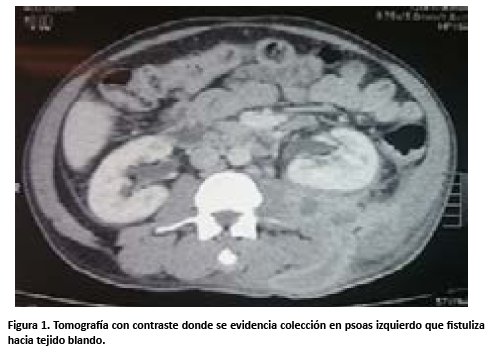

Se solicita tomografía contrastada, la cual informa colección de paredes gruesas que diseca las fibras musculares del psoas izquierdo y que se extiende hacia la pared ipsilateral y fistuliza a los tejidos blandos adyacentes (Ver figura 1), sin comprometer cápsula renal y con realce periférico tras inyección del contraste, resto de órganos sin alteraciones. Con los resultados de los exámenes auxiliares se plantea el diagnóstico sugestivo de absceso de psoas izquierdo.